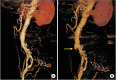

Methods: We retrospectively reviewed the database of patients who underwent OSC after EVAR from 2005 to 2018 in a single institution. Twenty-six OSCs were performed in 24 patients (median age, 74.5 years; 79.2% of males) who had undergone standard EVAR. We investigated pre-, intra-, and postoperative computed tomography or angiographic images and outcomes of the OSCs.

Results: Two main indications for OSC were persistent endoleak (50.0%) and endograft infection (EI) (38.5%). All 13 patients who underwent OSC due to endoleaks received EVAR outside of indications for use. Among 10 patients who underwent OSC due to EI, we found overlooked infection sources in 7 (70.0%) at the time of EVAR or during the surveillance period. OSC was performed at a median of 31.8 months (interquartile range, 9.4-69.8) after EVAR as an emergency (15.4%) or elective (84.6%) surgery. Aortic endograft was removed in 84.6% of cases (totally, 57.7%; partially, 26.9%), whereas it was preserved in 4 cases (15.4%). After 26 OSCs, 2 early deaths (7.7%) and 2 aortoenteric fistulae (7.7%) developed as major complications.

Conclusion: OSC after EVAR was associated with relatively higher perioperative morbidity and mortality. To avoid OSC after EVAR, we recommend careful assessment of coexisting infection sources and avoidance of EVAR for patients with especially unfavorable anatomy for EVAR, particularly the in proximal neck.